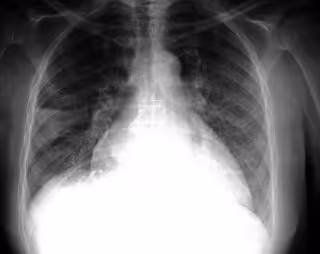

Respirar 'a ritmo de velcro', clave en el diagnóstico de la fibrosis pulmonar idiopática

FLICKR/PULMONARY PATHOLOGY/CC BY-SA 2.0

La fibrosis pulmonar idiopática es una enfermedad respiratoria que afecta a unos 7.500 personas en España y para poder combatirla es clave el diagnóstico precoz, que puede facilitarse mediante diferentes medidas como la presencia de 'crepitantes velcro' al auscultar al paciente.